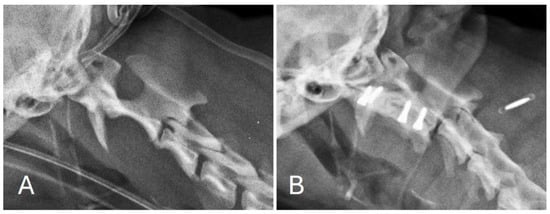

Post-operative images showed correct implant positioning and normal location of the dens within the respective fovea along the ventral arch of C1 (Figure 3 and Figure 4).

Figure 4. Sagittally reconstructed pre-operative (A) and post-operative (B) CT images of the atlantoaxial region.